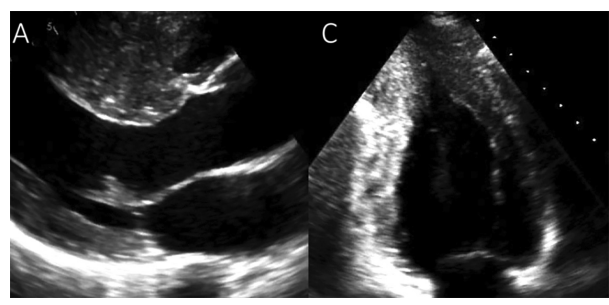

Tamponamento cardíaco é uma condição ameaçadora à vida, causada pelo acúmulo de líquido no saco pericárdico que comprime as câmaras cardíacas e inibe o enchimento normal. Quando o tamponamento é suspeitado, o ecocardiograma bidimensional deve ser obtido em caráter de emergência.

Nesse contexto, assinale a alternativa correta.